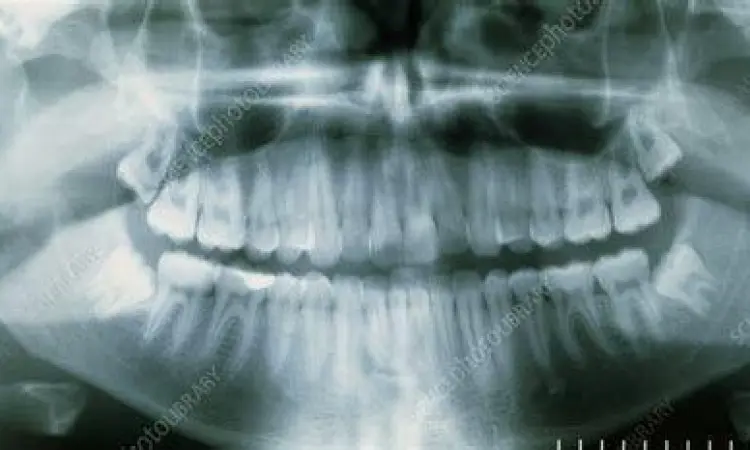

"Pencegahan jauh lebih baik daripada mengobati. Deteksi dini posisi gigi bungsu melalui rontgen panoramik sejak usia 16 tahun dapat menghindarkan pasien dari komplikasi bedah yang lebih rumit di masa depan."

Rekomendasi terbaik adalah melakukan pemeriksaan radiologi panoramik bahkan sebelum gejala muncul. Dengan melihat arah pertumbuhan sejak dini, dokter dapat memprediksi apakah gigi tersebut akan tumbuh normal atau menimbulkan masalah di kemudian hari. Keputusan untuk melakukan tindakan preventif sering kali memberikan hasil jangka panjang yang lebih baik bagi kesehatan fungsional dan estetika rongga mulut Anda. Ingatlah bahwa menjaga kesehatan gigi bungsu adalah investasi untuk kualitas hidup dan kenyamanan makan Anda di masa tua nanti.